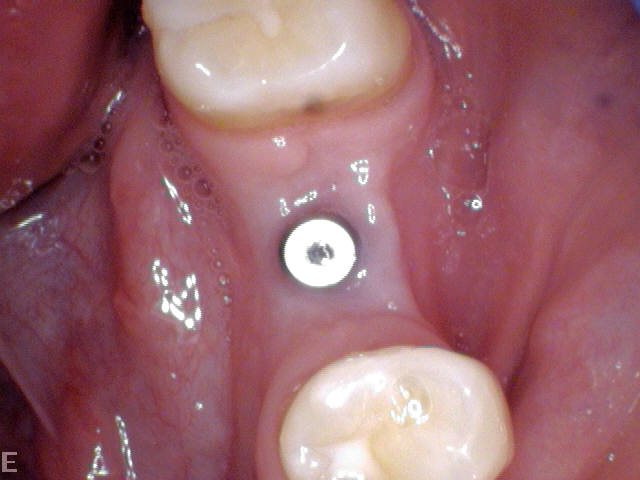

AfterDental Implants

Before

Before After

AfterVeneers